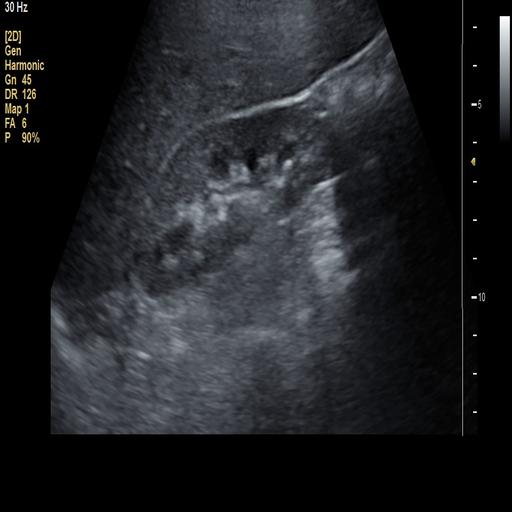

数据样例

结石肾脏样例